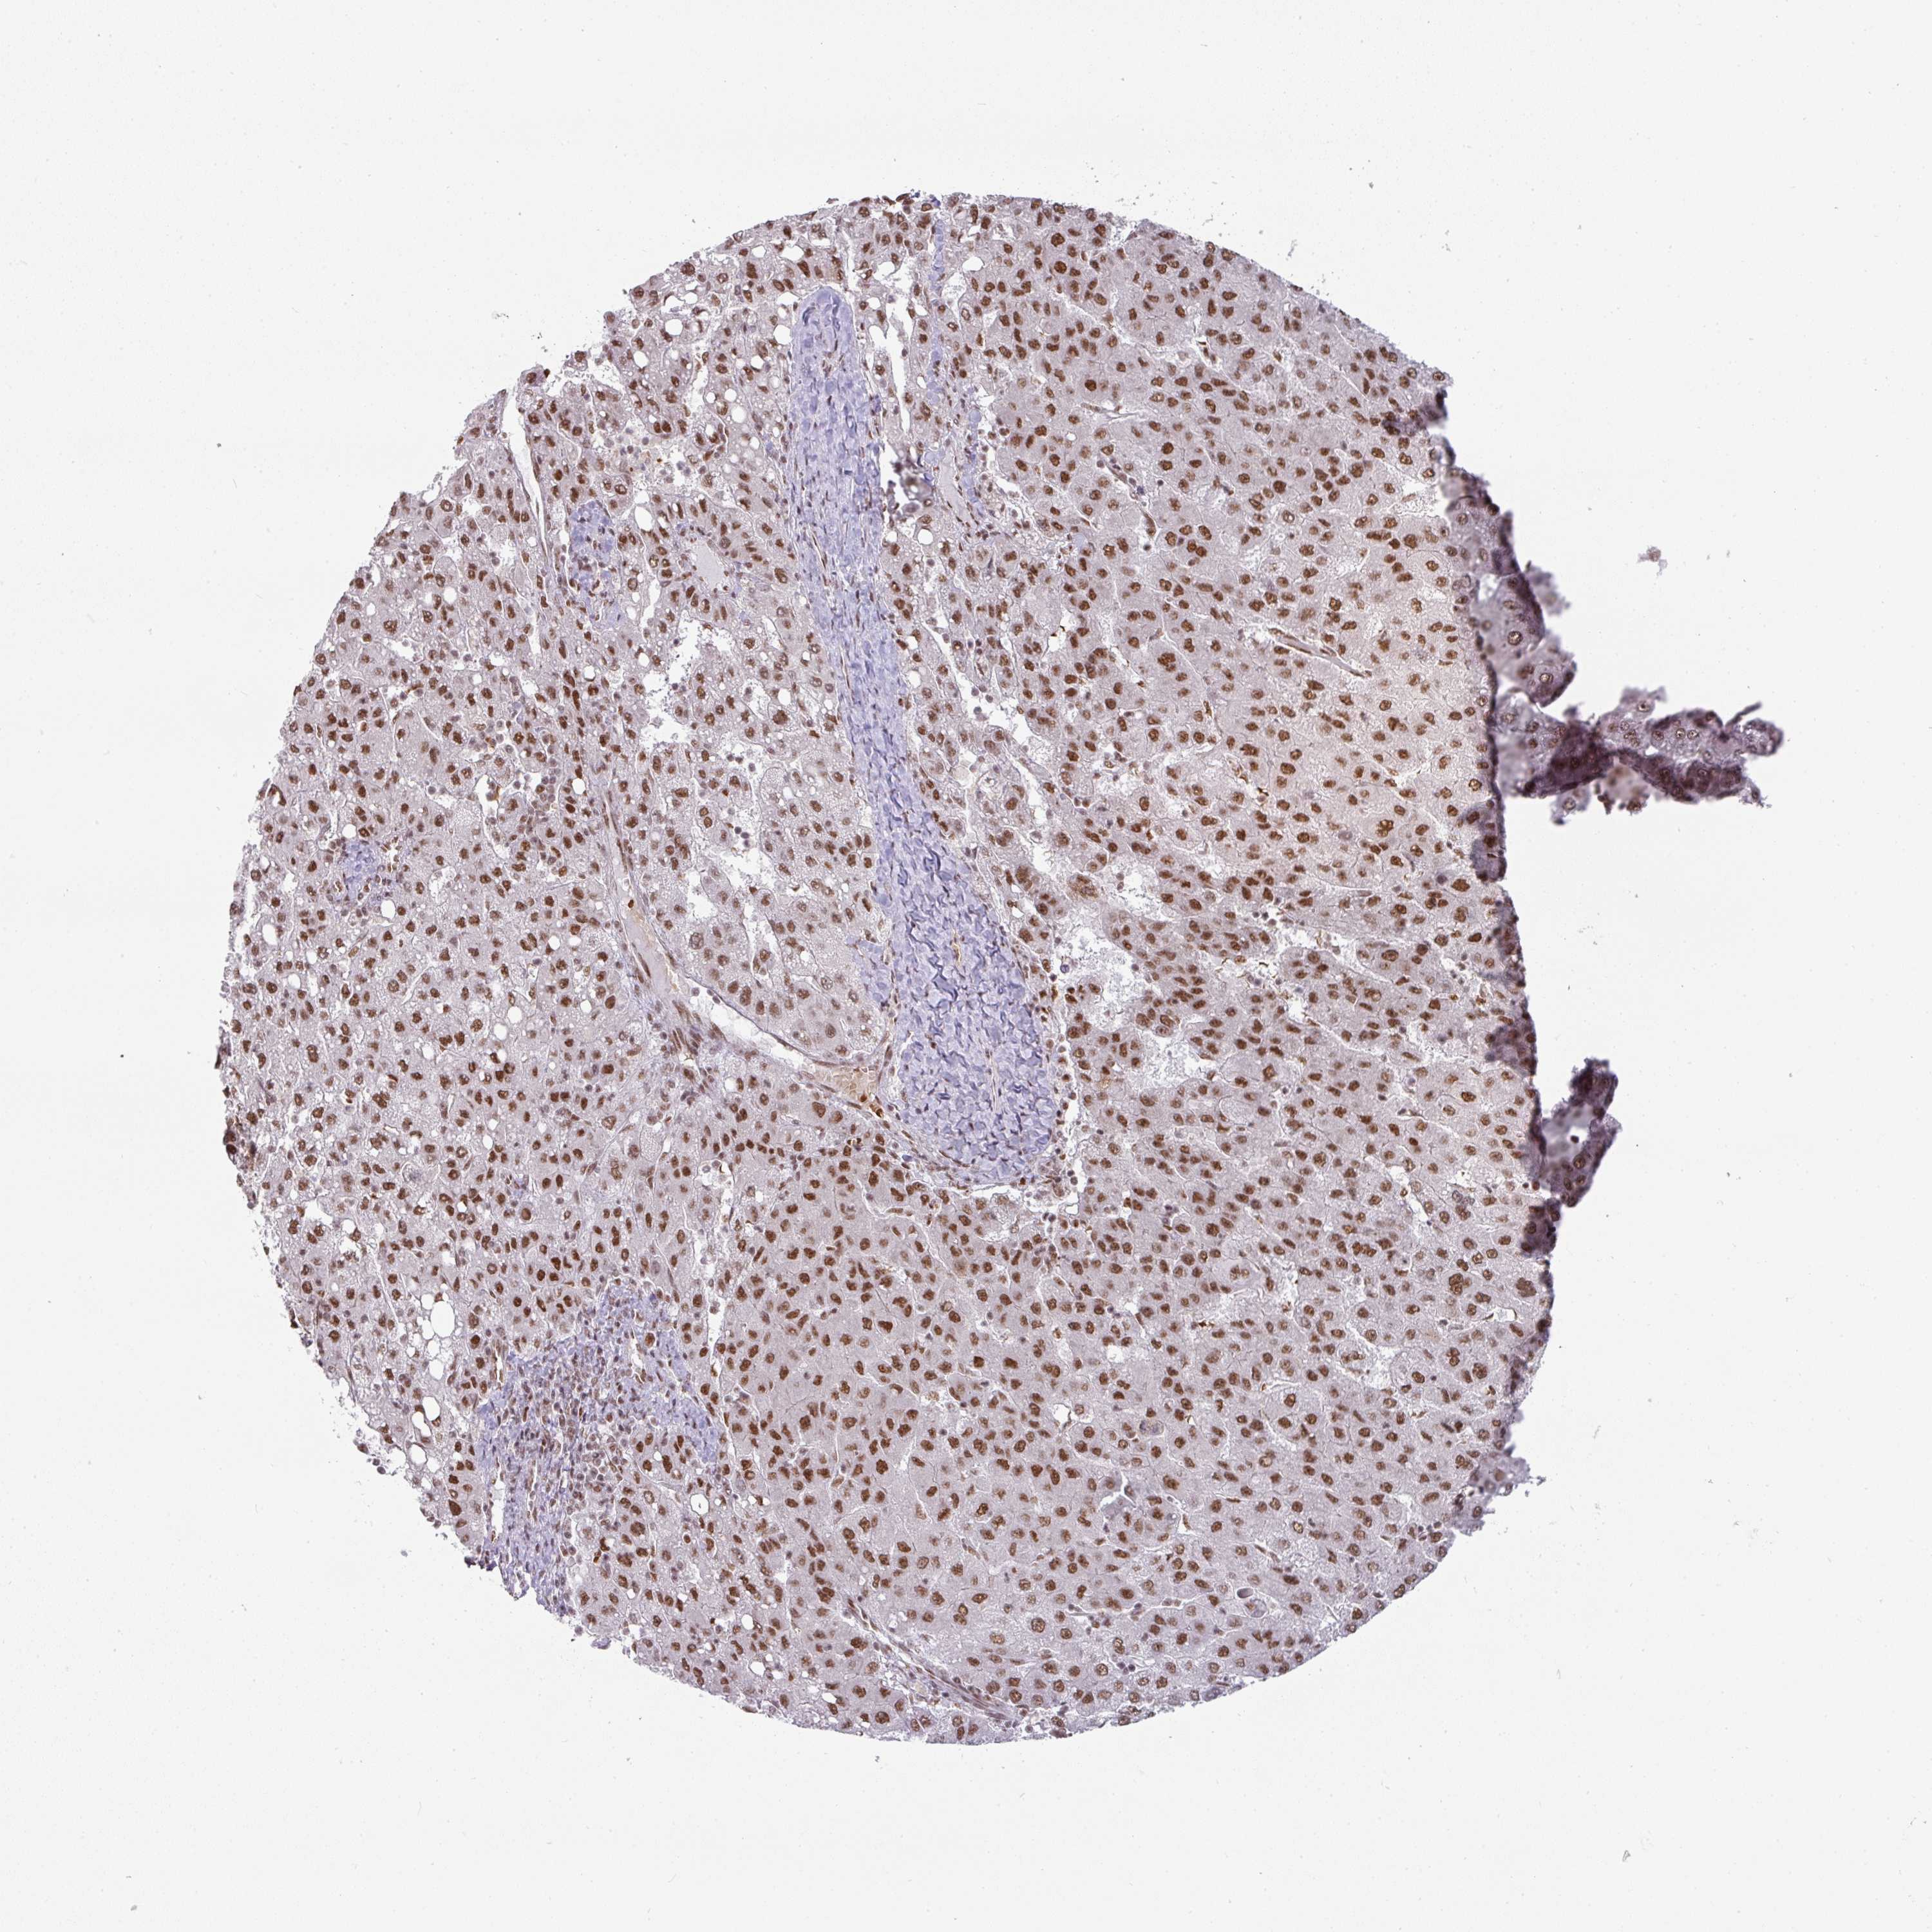

LIVER CANCER - Protein expressioni

A mouse-over function shows sample information and annotation data. Click on an image to view it in a full screen mode. Samples can be filtered based on level of antibody staining by selecting one or several of the following categories: high, medium, low and not detected. The assay and annotation is described here.

Note that samples used for immunohistochemistry by the Human Protein Atlas do not correspond to samples in the TCGA dataset.

Antibody stainingi

Antibody staining in the annotated cell types in the current human tissue is reported as not detected, low, medium, or high, based on conventional immunohistochemistry profiling in selected tissues. This score is based on the combination of the staining intensity and fraction of stained cells.

Each image is clickable and will lead to virtual microscopy that enables deeper exploration of all samples and also displays staining intensity scores, fraction scores and subcellular localization as well as patient and tissue information for each sample.

Antibody HPA050231

Staining

High

Medium

Low

Not detected

Intensity

Strong

Moderate

Weak

Negative

Quantity

>75%

75%-25%

<25%

None

Location

Nuclear

Cytoplasmic/membranous

Cytoplasmic/membranous,nuclear

Carcinoma, Hepatocellular, NOS